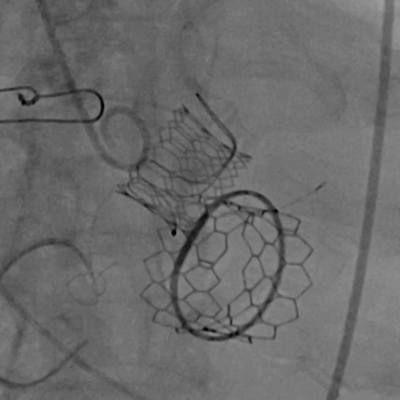

球扩释放二尖瓣环中瓣

黄焕雷主任带领具有丰富经验的心脏麻醉医师、体外循环师、超声心动图医师、手术室、心外重症监护室、心脏导管室多学科团队,联合心内科专家谢年谨主任,为蔡先生实施小切口下、介入途径的主动脉瓣“瓣中瓣”、二尖瓣“环中瓣”的同期植入手术:黄主任首先在患者左前胸做一小切口,暴露患者的心尖,在跳动的心脏上“绣”上荷包作为介入导管、瓣膜的植入“门户”;随后,黄焕雷主任在超声心动图、放射透视的引导下,将一钢针在患者心尖“扎”入患者心脏内,为之后的瓣膜植入作为引导,具体来说就是将预先选择适合患者大小的生物瓣膜折叠、压缩入细长的输送管道内,好比将瓣膜这一“弹头”安放在输送导管这颗精准制导的“火箭”上,而黄主任的双手则控制这一精准发射和制导,再将瓣膜输送到主动脉合适的位置后释放,新的主动脉瓣便牢固地“卡”在了原有的主动脉瓣架内。经过透视和超声心动图评估,主动脉瓣位置合适,开放、闭合功能良好。随后,黄主任通过这一根钢针和输送导管,利用类似的方式,调整“火箭”的发射轨道,在原有二尖瓣人工瓣环内植入预先选择好大小的二尖瓣生物瓣膜,经过影像学方式评估,新植入的二尖瓣生物瓣工作良好。